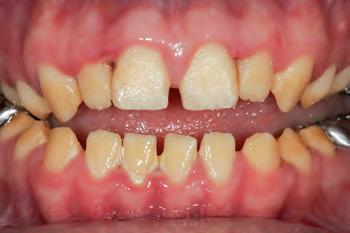

The patient was an 18-year-old male with a confirmed family history of Xlinked AI, who was otherwise in good health and non-smoking. Upon initial clinical presentation, a low-caries-risk, complete adult dentition from second molar to second molar was present, which was globally affected by pitted, hypoplastic and hypomineralised AI, dento-alveolar disproportion and an unusual generalised open occlusion, characterised by one occlusal contact at the right first molar region in the maximum intercuspation position (MIP). Historical paediatric management of the dentition involved placement of stainless steel crowns at the first permanent molar sites to protect the emerging dentition from post-eruptive breakdown and loss of occlusovertical dimension during the mixed dentition phase.6 On adult presentation, all but the UR6 stainless steel crown remained intact. Oral hygiene was poor, with evidence of plaque-induced chronic gingivitis (Figure 1). The patient reported experiencing severe, widespread hypersensitivity upon hot, cold, osmotic and masticatory stimuli, and feeling aesthetically self-conscious. The patient was seeking comprehensive fixed prosthodontic care and was well informed about the nature of such treatment, having witnessed his elder siblings undergo similar treatment.

1: The patient’s initial situation on clinical presentation to the tertiary care referral centre. The dentition is globally af fected by amelogenesis imperfecta, associated with dentoalveolar disproportion and an unusual presentation of open occlusion.